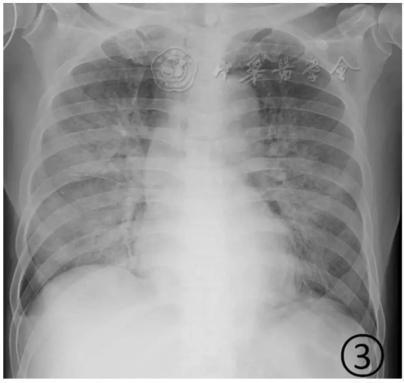

按照國家衛健委發布的新型冠狀病毒肺炎試行第六版診療方案之中的臨床分型,新冠肺炎分為輕型、普通型、重型及危重型。在患者的肺部CT中,輕型者沒有比較明顯的肺炎改變;普通型者以肺部出現局限性斑片狀或很多節段性片狀“病灶”為主(圖②);重型者雙肺可出現較多的白色小斑片“病灶”,部分融合成大片狀“病灶”(圖③);危重型者會有“白肺”表現(圖④)。

▲從上到下依次為普通型、重型及危重型新冠肺炎患者的肺部CT表現(圖片來自網絡)